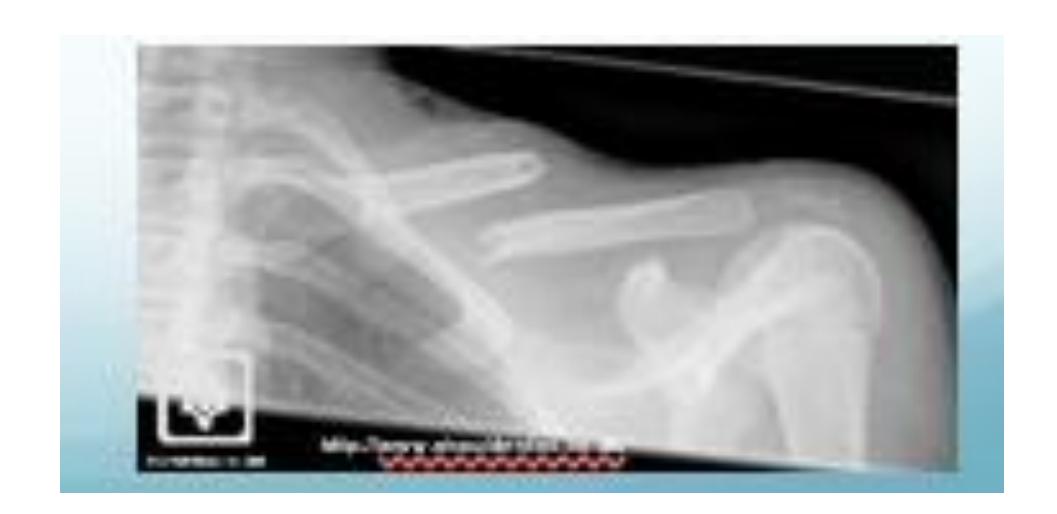

Anterior Shoulder Dislocation

What is the diagnosis shown in the image?

- Anterior Shoulder Dislocation

What is the most common complication of anterior shoulder dislocation?

- Axillary nerve injury